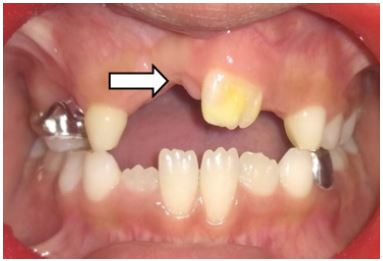

Extraorally, there were no significant findings (Figure 1). Intraorally, patient had mixed dentition with missing maxillary incisors but had slight elevation of left anterior alveolar ridge in the region of left maxillary central incisor (Figure 2a and 2b). Provisionally it was diagnosed as an odontome in maxillary anterior region.

Figure 2: (A) Showing the teeth in occlusion. (B) Showing maxillary arch.